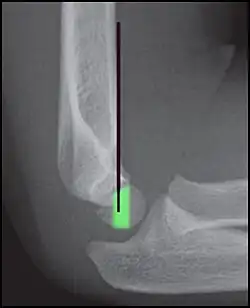

Anterior humeral line - It is a line drawn down along the front of the humerus on the lateral view and it should pass through the middle third of the capitulum of the humerus.[9] If it passes through the anterior third of the capitulum, it indicates the posterior displacement of distal fragment.[8]

Anterior humeral line (black line), with normal area passed on the capitulum of the humerus colored in green in a 4-year-old child.[9] -

The anterior humeral line is not reliable in children with sparse ossification of the capitulum, such as in this 6 months old child.[9]